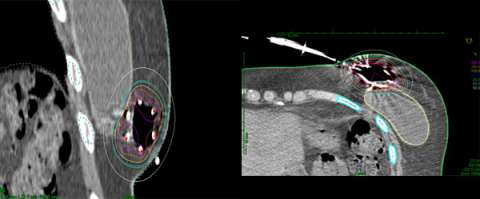

Examples show how the radiation dose (the colored lines, with the white lines representing 50% of the dose) is targeted to the area where the original tumor was using three different partial breast radiation techniques (SAVI, Contura, Tube and Button).

This is in contrast to these examples of standard whole breast radiation where the entire breast is considered the target.